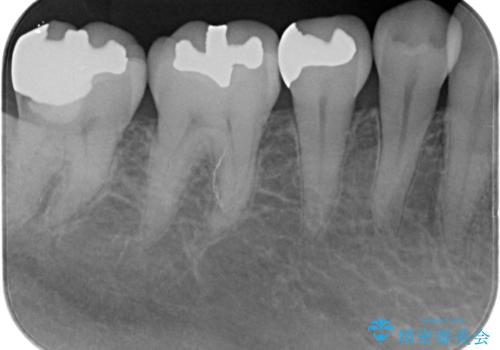

- 右下奥歯が気になるとのことで来院された患者様です。

銀の詰め物の適合が悪く、歯と銀歯の間に歯茎が入り込んできている状態でした。

銀歯を除去し、適合の良いゴールドアンレーで修復していきます。